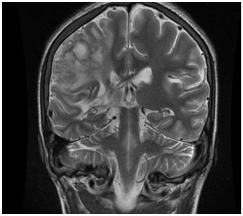

We present the case of a 16-year-old male patient, born in Veracruz Mexico with history of pulmonary stenosis, hypoplastic right ventricle, interauricular communication and patent ductus arteriosus who had surgical intervention with Blalock Taussig shunt on November of 2003. On July 11th 2016 he started with numbing of the left half of his face including the tongue, for which he didn’t seek any medical attention. On July 18th 2016 he had a generalized seizure, which lasted 10 minutes, according to his family. On July 28th 2016 he started to lose strength of the left half of his body and wasn’t able to walk or move his left arm. With these symptoms he was admitted to our hospital where he also referred headache. CT scan showed hypodense images on right temporoparietal region and reinforcement images on right parietal region suggesting brain abscesses (Figure 1 & 2). With these findings, along with the clinical presentation, the diagnosis of brain abscess was made and antibiotic treatment was started with third generation cephalosporin, metronidazole and glucopeptide. The patient was evaluated by the neurosurgery team who decided to differed surgical treatment because of the size of lesions in CT scan and improvement in next CT scan images. On August 8th 2016 a MRI (Figure 3) of the brain showed capsule formation. The patient continued with antibiotic treatment and dexamethasone in reduction dose. A new MRI of the brain, on August 29th 2016, showed abscesses of less than 3 cm, this along with the patient improving neurological state and decide no need for surgical treatment. The patient completed 61 days of parenteral treatment with ceftriaxone, metronidazole and vancomycin. The last imaging study previous to the discharge of the patient showed brain abscesses of less than 0.5 cm.

Figure 3